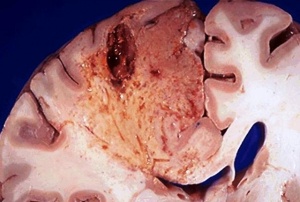

Столичен лекар от Спешна помощ бе отстранен от длъжност. Той по погрешка диагностицирал грип вместо реалното състояние на пациента – инсулт. Пациентът е приет в болница в критично състояние и има минимален шанс за оцеляване.

Заради грешната диагноза лечението на 50-годишния Красимир Петров се забавило с три часа. В момента той се намира в Окръжна болница и е в критично състояние, като лекарите дават 5% шанс за оцеляването му, допълва News.bg.